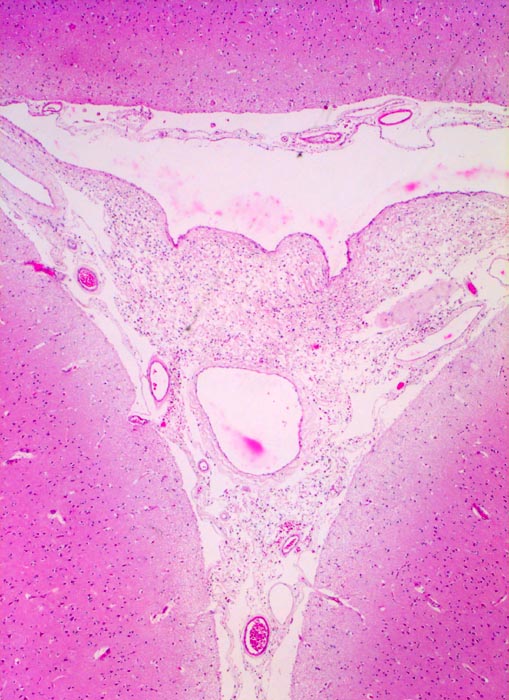

Das Meningeom zeigt ein grosses Spektrum histologischer Varianten mit sehr unterschiedlicher Morphologie. Am häufigsten sind meningotheliale (ihr Präparat), transitionale und fibroblastische Meningeome. Typisch für das meningotheliale Meningeom sind dicht gepackte Zellen mit unscharfen Zytoplasmagrenzen, Wirbelbildungen und Kerne mit intranukleären Vakuolen. Ferner finden sich konzentrische Verkalkungen in Form von Psammomkörperchen (> 255).

Morphologische Merkmale:

• Kugelige Tumorzellverbände mit Ausbildung von typischen konzentrischen zwiebelschalenartigen Formationen und parallele Bündel spindeliger Zellen.

• Tumorzellen mit ovalen Kernen ohne Atypien und reichlich Zytoplasma. Keine Mitosen.

• Psammomkörperchen (konzentrisch geschichtete Verkalkungen).